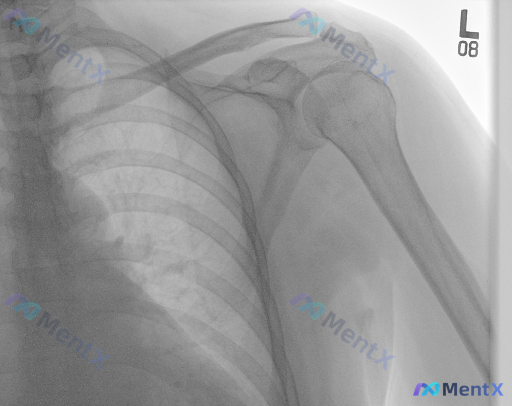

整理了一份有意思的影像讨论资料: 左侧肩部正位X光,常规读片结果是: - 肱骨近端、肩胛骨、锁骨远端未见明确骨折线 - 盂肱关节对位良好,无脱位 - 骨密度、关节间隙、肩峰形态大致正常 - 大结节上方未见明确钙化影,软组织轮廓尚可 但设定明确提示——「存在异常」。 这种「X光报“未见明显异常”但实际...

整理了一张左肩关节正位X光片的资料,想和大家讨论一下读片思路。 基础影像表现: - 肱骨近端、肩胛骨、锁骨远端:未见明确骨折线、骨皮质中断,也没有明显的溶骨/成骨破坏 - 盂肱关节:对位良好,关节间隙宽度正常 - 软组织:肩部周围未见明显肿胀、钙化 - 唯一明确的阳性发现: 肩胛部及胸壁周围软组织区...